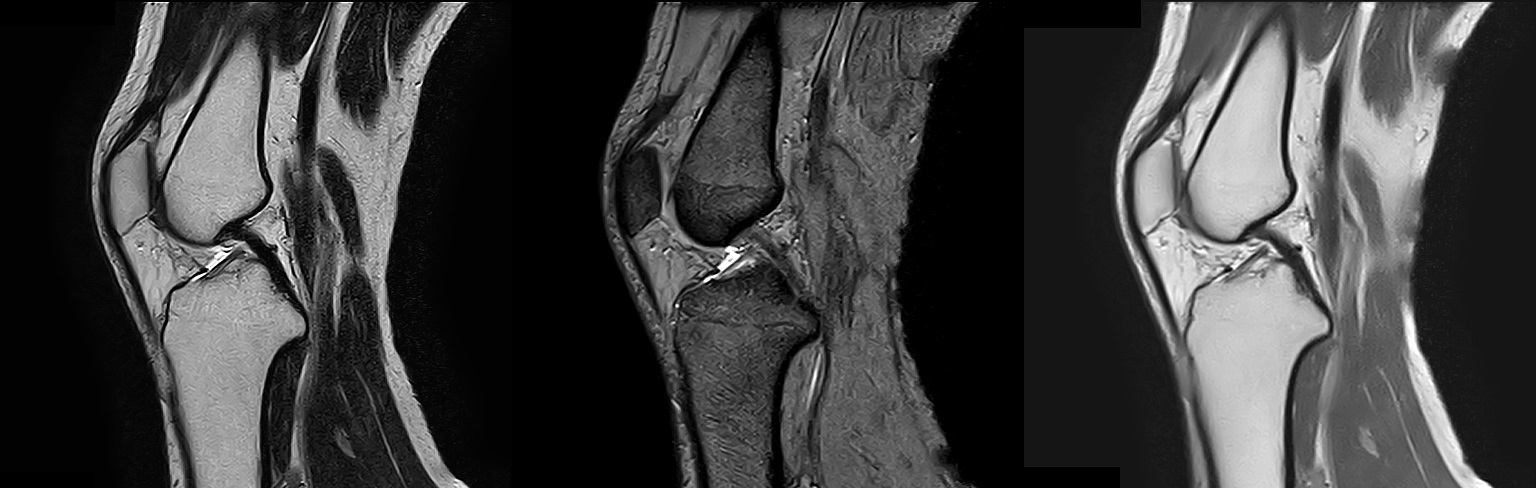

1.5テスラMRI(磁気共鳴画像)装置

2022年2月にMRI装置を更新いたしました。

1.5TのMRI装置(富士フイルムヘルスケア株式会社製「MRイメージング装置 ECHELON Smart」)を導入し、以前よりも短い時間で高画質の撮像が可能になりました。

MRIは体内の断面像を縦、横、ナナメから人体に悪影響を与えずに見ることが出来る装置です。わずかな病変も見逃さない鮮明な画像は腫瘍などの早期発見や健診に威力を発揮します。薬品を全く用いずに血管撮影等が出来るので、患者さんは動かずに横になるだけで苦 痛なく精密検査が受けられます。

検査をご希望される方は医師へお気軽におたずね下さい。

MRA

頭部

T1強調像 / T2強調像 / FLAIR像 / T2*強調像

T2強調像 / T2*強調像 / プロトン密度強調像